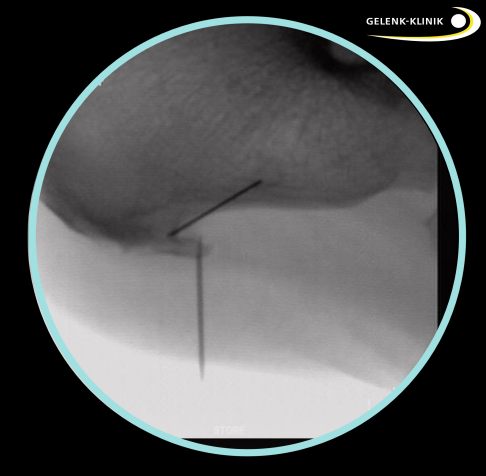

Unter Röntgenkontrolle mit einer beweglichen Röntgenröhre (Bildwandler) lokalisiert der Fußspezialist den Fersensporn und markiert ihn mit einer Nadel. Dann führt er über zwei kleine Hautschnitte eine Kamera mit Lichtquelle und spezielle chirurgische Instrumente ein. Durch die Nadelmarkierung kann der Fersensporn leicht gefunden und dargestellt werden. Mit einer kleinen Kugelfräse entfernt der Operateur den knöchernen Vorsprung. Dann glättet er das Fersenbein vollständig, um eine weitere Reizung und Entzündung der Sehnen zu verhindern.

Postoperative Röntgenkontrolle: Nach der Operation bestätigt eine Röntgenkontrolle das Ergebnis. © Gelenk-Klinik